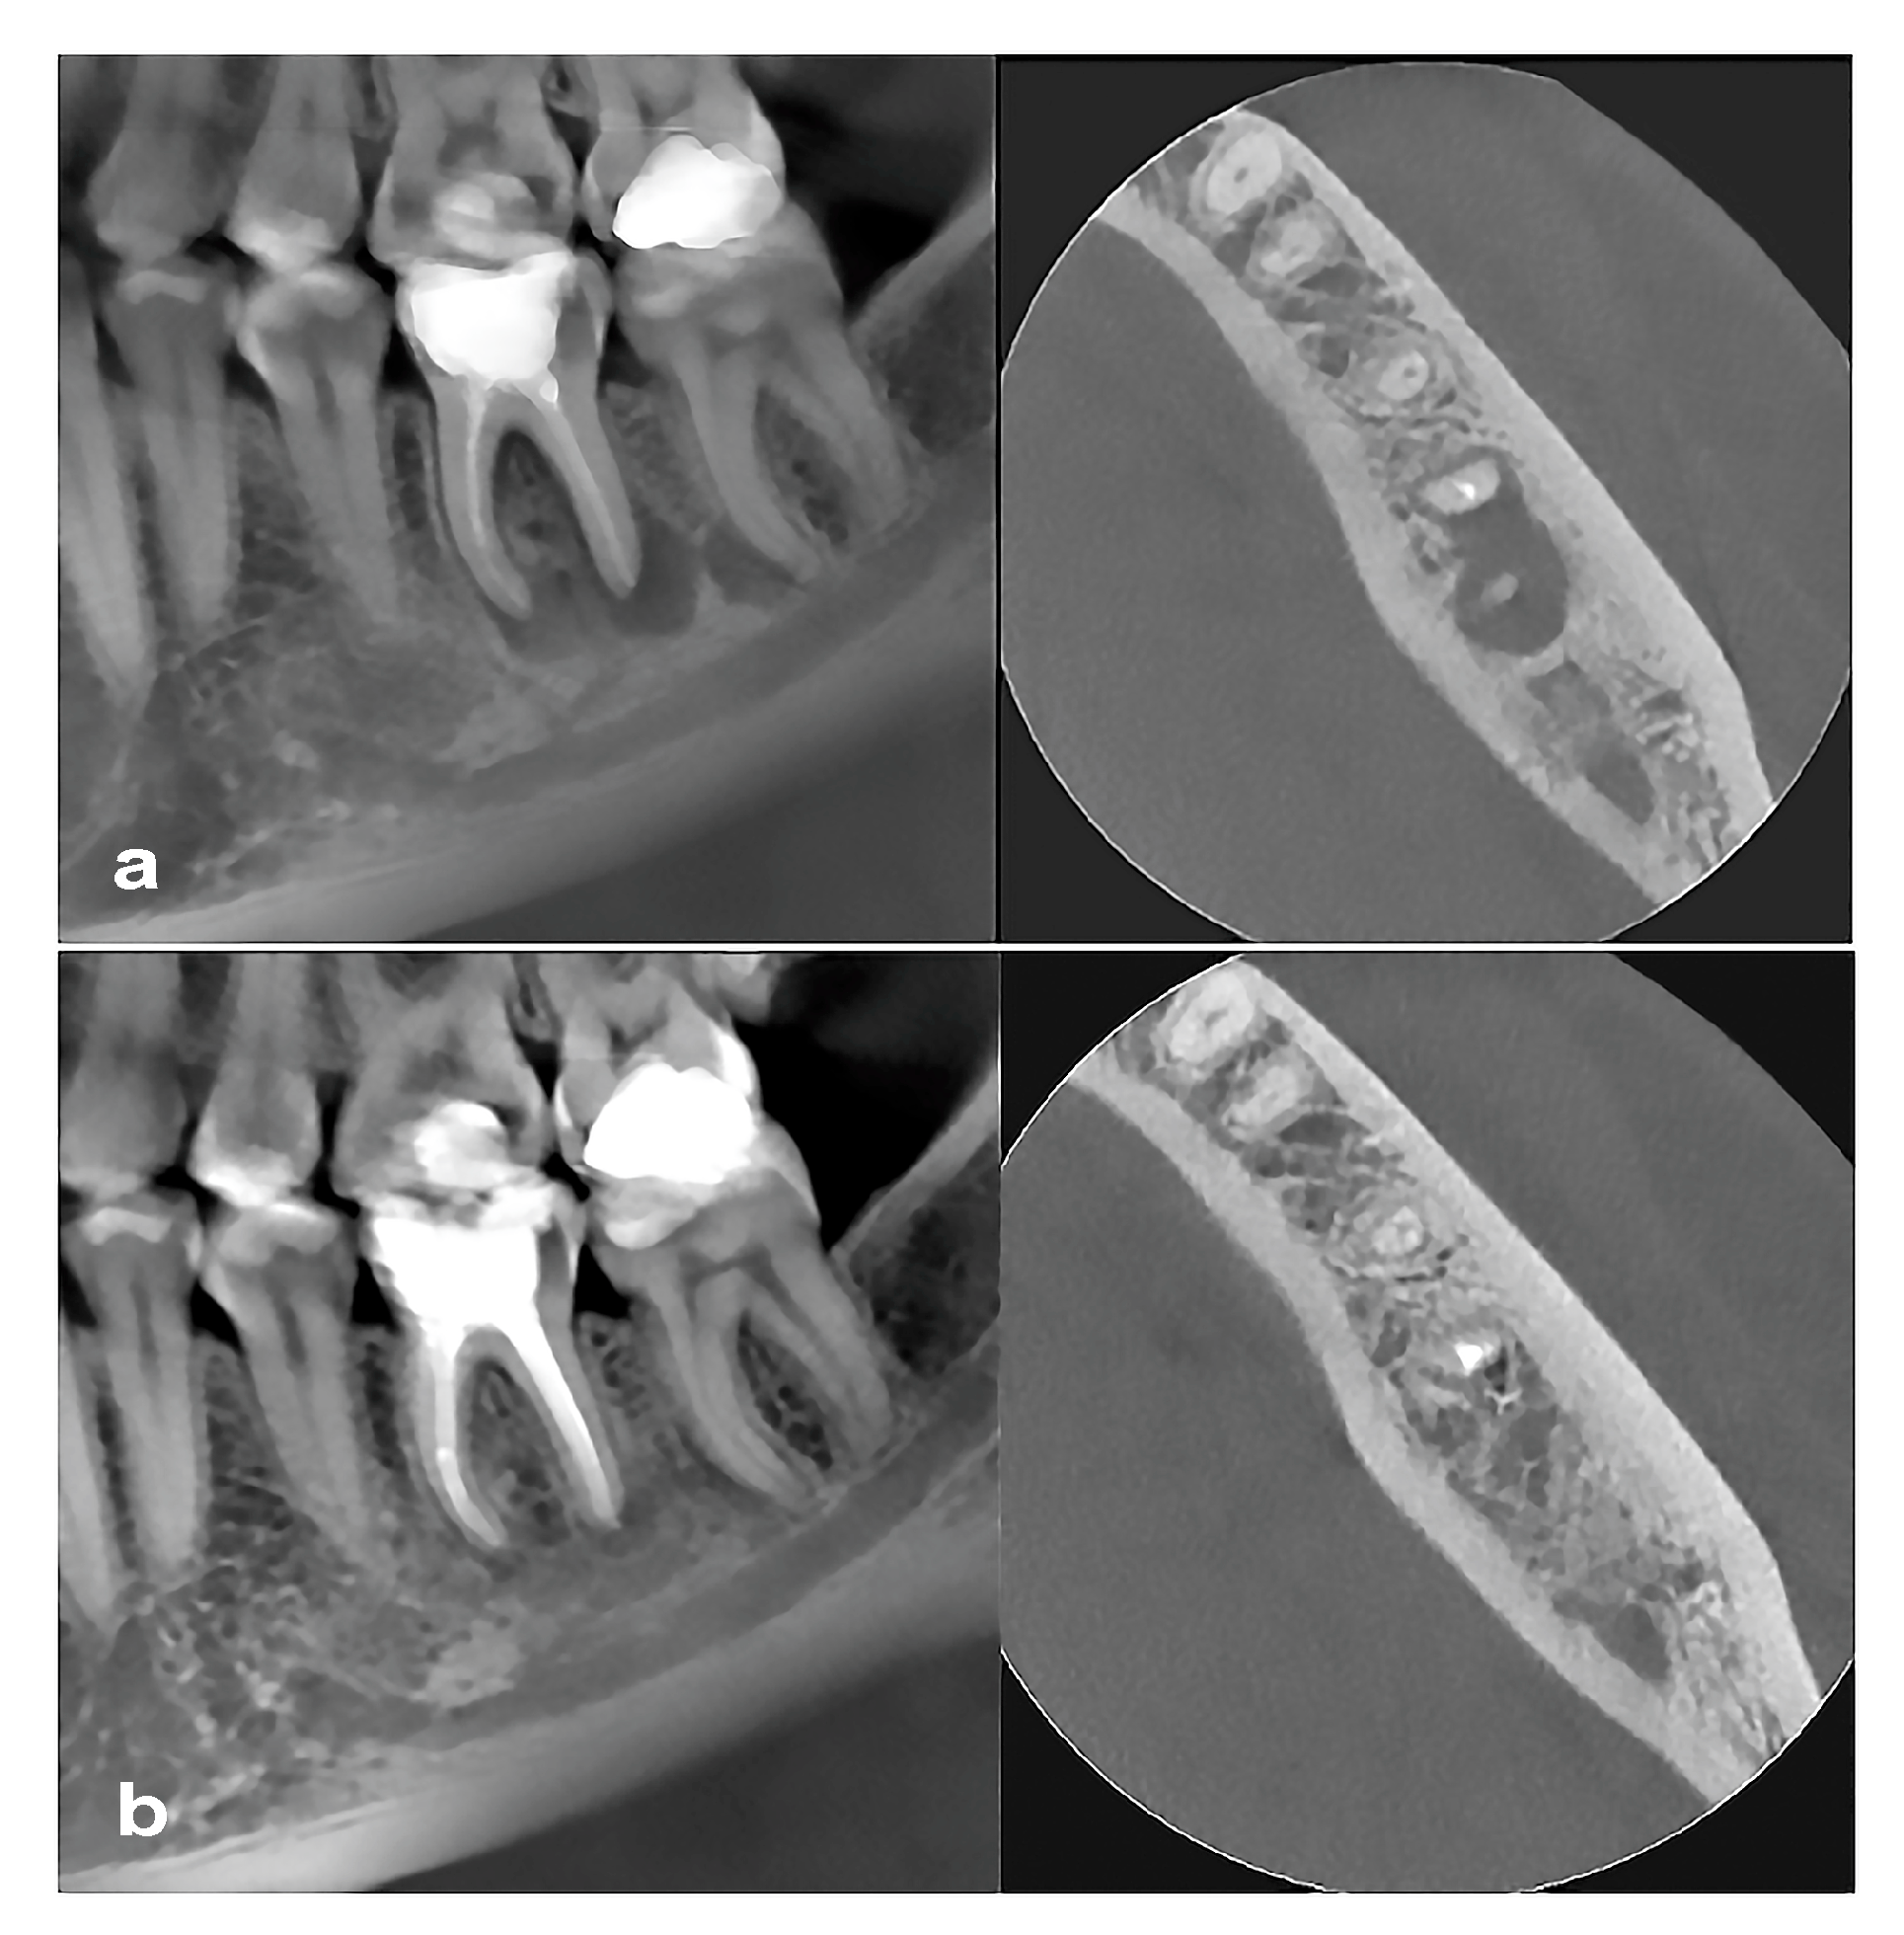

2.5. Cone Beam Computed Tomography Evaluation